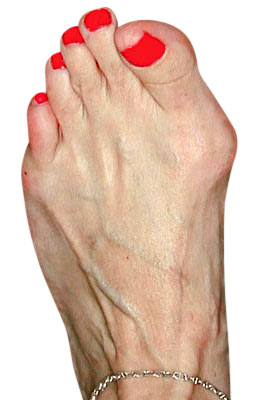

Before

Minimally Invasive Bunion Surgery before

After

Minimally Invasive Bunion Surgery after

Minimally Invasive Bunion Surgery featuring the miniBunon™ System and Tailors Bunionectomy

Melissa is a 32-year-old businesswoman who could not be off her foot post-surgery, yet she had a severely painful bunion. We performed our miniBunon™ System (our trademarked minimally invasive bunion surgery) and had a dramatic correction with no downtime. Melissa continued to work after her bunion surgery and was back in shoes and full activity at 5 weeks. Melissa could not believe the results of her Bunionectomy resulting in no bony bump, no scar and amazing motion. “After” picture taken immediately following surgery. Note the bunion and bunionette (Tailor’s bunion) in the before picture.